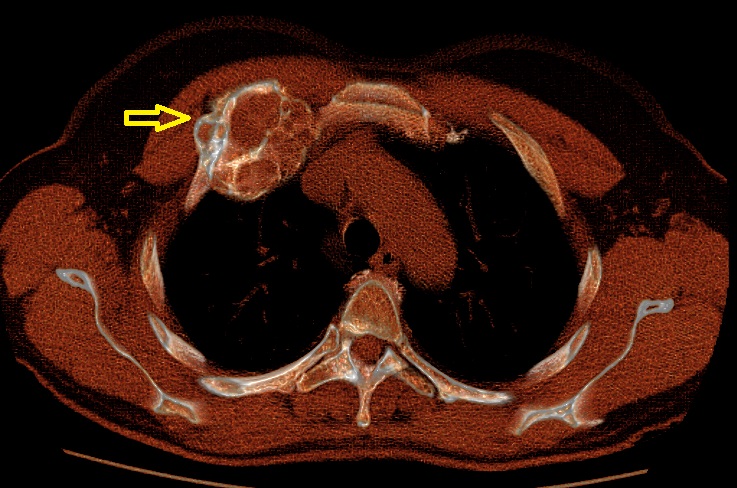

Tuttavia, nei casi più gravi che causano sintomatologia significativa o deformità (Figura 3), potrebbe essere necessario un intervento chirurgico per rimuovere il segmento osseo o i segmenti ossei interessati (Figura 4) e stabilizzare le strutture ossee residue, riducendo il dolore e migliorando la funzionalità.

TAC Torace che mostra una displasia fibrosa gigante

TAC Torace che mostra una displasia fibrosa gigante a partenza dalla II costa di destra in sede parasternale (freccia)